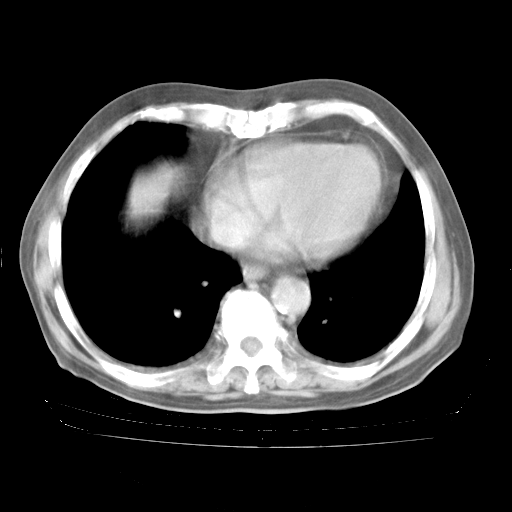

今天部分检查

轻微咳嗽,无痰,(体温正常时)R20次/分,P75次/分,双肺底、腋下可闻及少量捻发音。下肢轻度浮肿。

血常规:白细胞9.11×109/L,N0.92,L5.64,血小板39.2×109/L,HB148g/L,ESR2mm/H。

尿常规:潜血+

血生化:总蛋白69.71g/L,白蛋白38.40g/L,球蛋白31.31g/L,CRP27.9mg/L,尿素氮11.98mmol/L,肌酐106μmol/L,乳酸脱氢酶1099 U/L,肌酸激酶108U/L,CK-MB 61U/L。

腹部B超:胆囊壁增厚,肝、胆、胰、脾、肾无异常,肠系膜淋巴结、腹膜后淋巴结无增大。

ECG:右心室增大

心脏超声检查:无右心室增大。

增加治疗:异烟肼、利福平、乙胺丁醇,静滴左氧氟沙星、参麦注射液。甲强龙从80mg暂减为40mg。

强的松3月1日改为10mg qd,4月1日改为10mg qod。3月份以前的减量过程和环磷酰胺疗程需等明天查看记录(我岳父自己做的记录在他家里)。